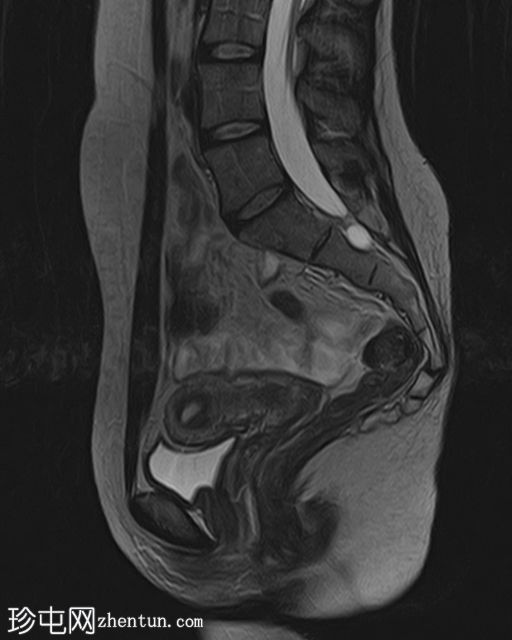

矢状位

T2

已确诊3例卵巢囊肿:

右侧卵巢出血性囊肿,T1成像呈中等信号,T2成像呈高信号,伴有薄内部分隔

左侧卵巢出血性囊肿,信号特征与右侧囊肿相似

左侧单纯性卵巢旁囊肿,T1成像呈低信号,T2成像呈高信号

此外,所有囊肿均未显示弥散受限或实性成分强化。

所有囊肿均仅显示薄层外周壁强化。

道格拉斯囊右侧可见轻度积液。

卵巢相关囊性病变边界相对清晰。信号特征可能因出血时间而异。

T2 加权成像通常显示高信号。 T2 阴影征提示存在慢性血液产物,更像子宫内膜异位症。

本例卵巢囊肿呈中等 T1 信号,类似于肌肉信号,T2 信号高,伴有薄内隔和外周壁强化。但无内部强化或弥散受限。STIR 序列显示与 T2 一致的信号,无任何脂肪成分。该表现提示卵巢出血性囊肿处于早期或消退期。

建议在下一个月经周期(通常在 6 至 8 周内)进行盆腔超声随访,以确保囊肿消退,因为大多数出血性囊肿往往会自行消退。如果病变持续存在或扩大,可能需要进一步评估。